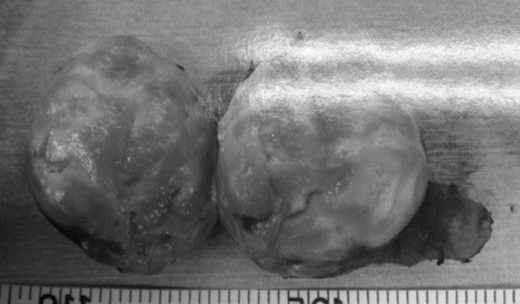

The intra-operative blood loss was minimal, and the operation time was 150 min. The specimen was an elastic hard, 5 × 4 cm mass with an integral envelope. On sectioning, it was yellow and white in color, predominantly solid with cystic change (Fig. 6). Pathologic examination showed whorls and interlacing fascicles of schwannoma spindle cells, along with alternating Antoni-A and -B patterns with areas of hyalinization and fibrinoid degeneration (Fig. 7a and b). The cells stained positive for S-100 protein and negative for desmin and muscle-specific actin, consistent with a benign schwannoma. The patient had an uneventful post-operative course and was discharged on the fourth post-operative day. The patient has had no evidence of recurrence so far, 20 months after surgery.

The specimen is an elastic hard, 5 × 4 cm mass with an integral envelope. On sectioning, it is yellow and white in color, predominantly solid with cystic change.